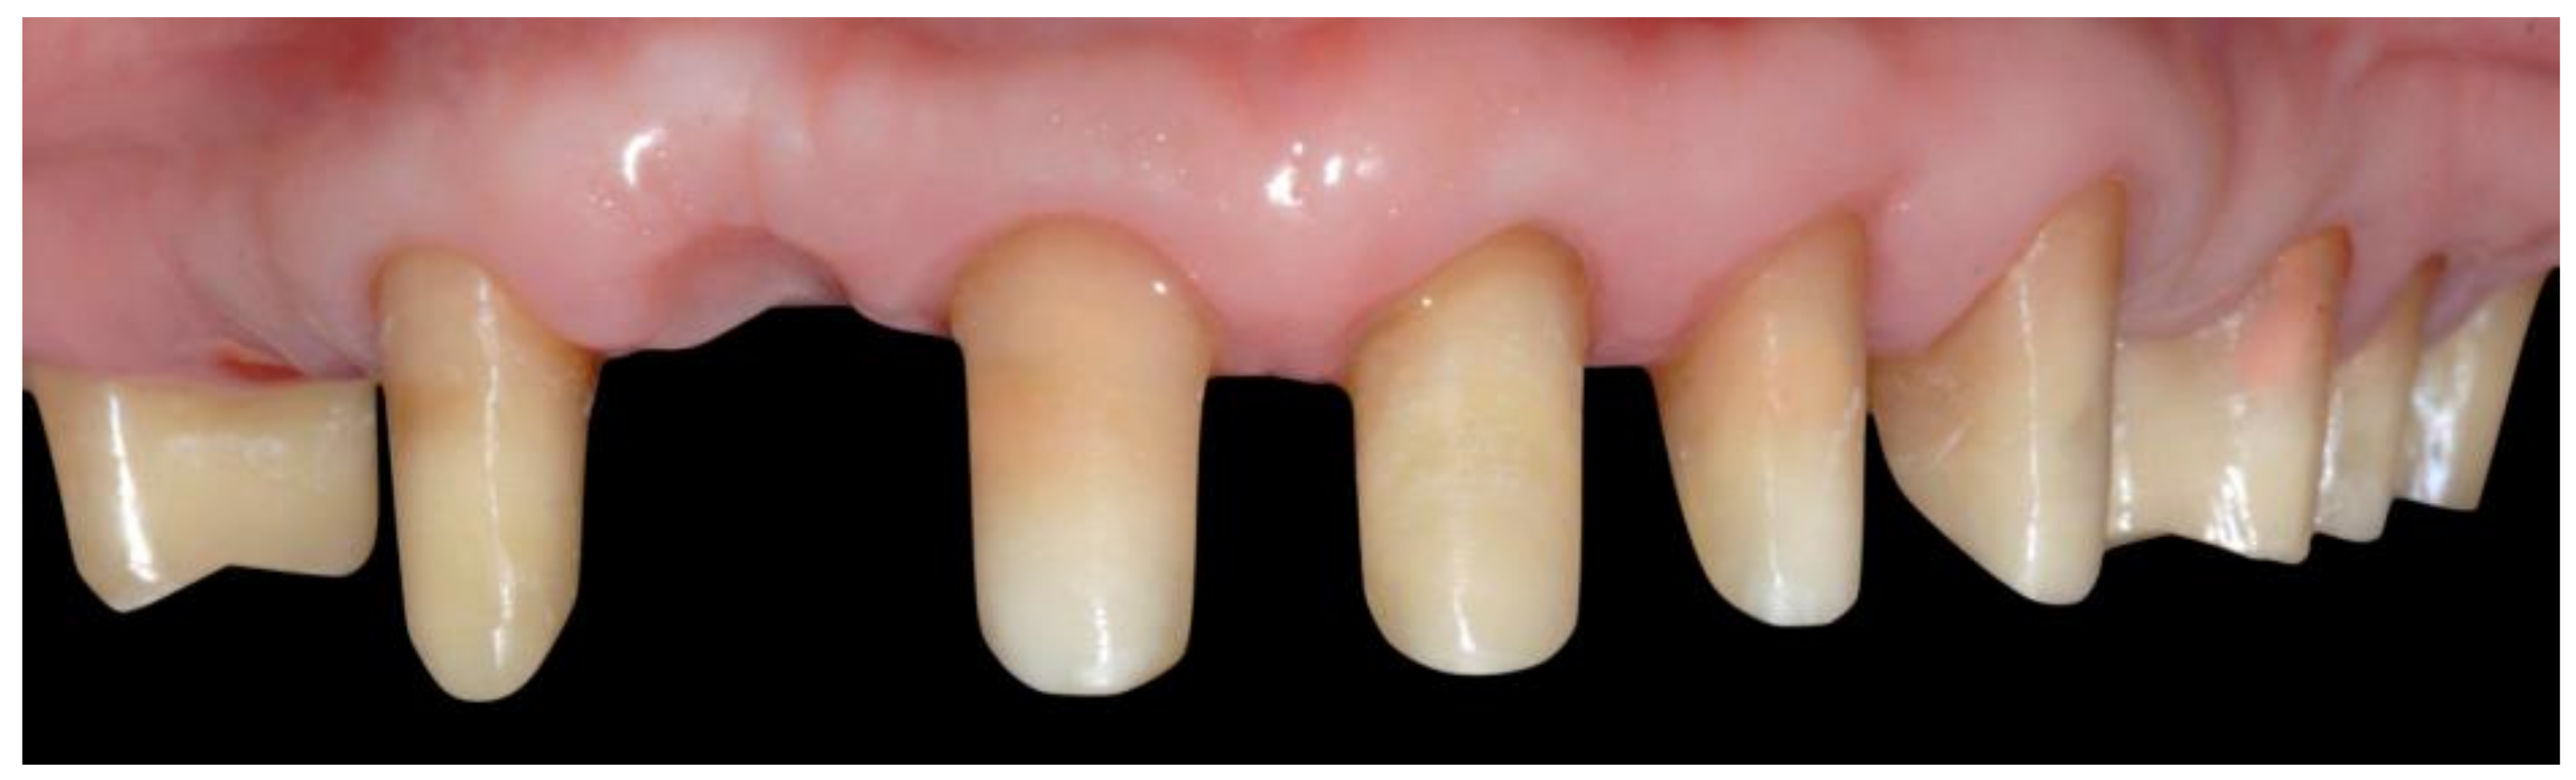

- Temporary crown relining and delivery: Next, the insertion and the housing of the temporary crown are checked and then relined. It is essential not to move the crown during the relining stage so that the margin will not open, guaranteeing an adequate closure (Figure 5). After that, refining is necessary, keeping the margin as thin as possible. After polishing, the temporary crown is cemented with eugenol-free temporary cement. With the VEP technique, as with the intraoperative preparation technique, the apical part of the abutment reached by the bur does not correspond with the prosthetic margins, both for the provisional crown and the ceramic one. The cervical margin of the temporary crown is placed coronally to the corresponding gingival margin to allow undisturbed healing of the soft tissues surrounding the abutment (Figure 6).